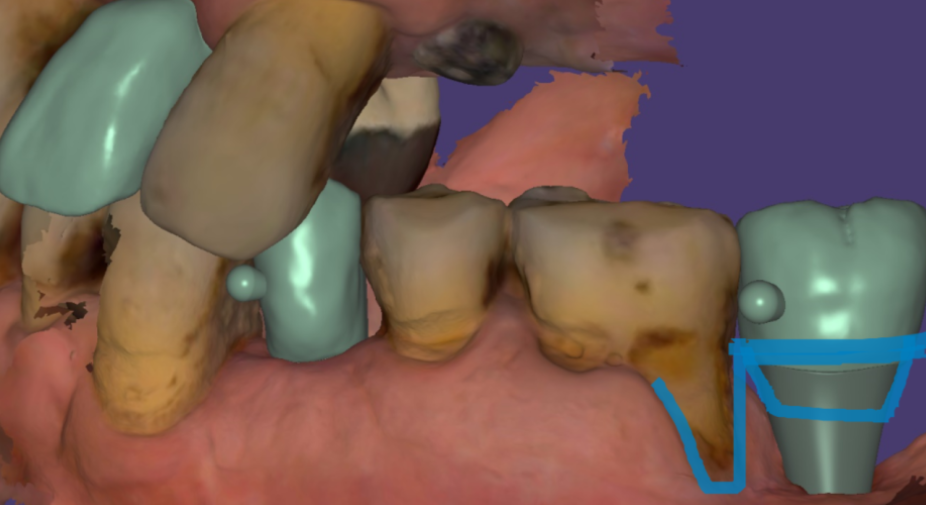

2️⃣임플란트 크라운 지르코니아

겉과 속 모두 하얀색깔입니다.

천호동 치과에서 제작하는

임플란트 크라운

보험 임플란트를 제외하고 지르코니아로 제작합니다.

이유는 간단합니다.

pfm의 단점을 극복했기 때문입니다.

예쁘고요

단단합니다.

또다른 이유로 제작 방식도 바르디치과가 추구하는

디지털 임플란트와 결이 맞습니다.

지르코니아는 3d 프린팅 기법으로 제작됩니다.

저희 병원의 장점 디지털 진료를 선두하죠?

스캐너로 뽄을 떠서

컴퓨터로 제작하니까!